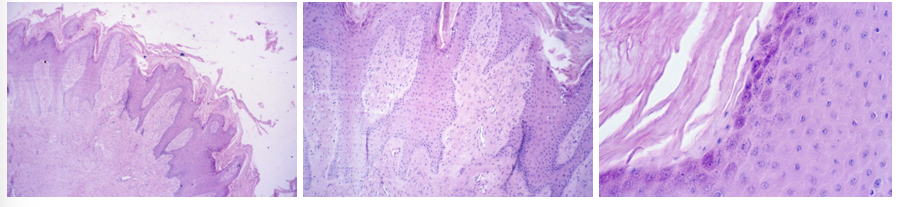

this is?

Fibroma molle

Description: Consists of fibrinous material, predominated by nuclei and plumb cell bodies. Cells with few fibrils run aimlessly in many directions. Mitosis is seldom. Tumor tissue is edematous permeated (no stained slots among individual cells) or infiltrated by heterophils, lymphocytes and macrophages (body reaction).

Etiology: Unknown

Pathogenesis: A benign mesenchymal tumor arising from fibrous connective tissue. Has 2 forms: Fibroma durum which is predominated by fibrous material, causing it to be hard. And fibroma molle, where cell bodies and nuclei predominate, which is softer due to fewer fibrils.